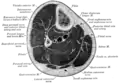

Secção transversa no meio da perna.